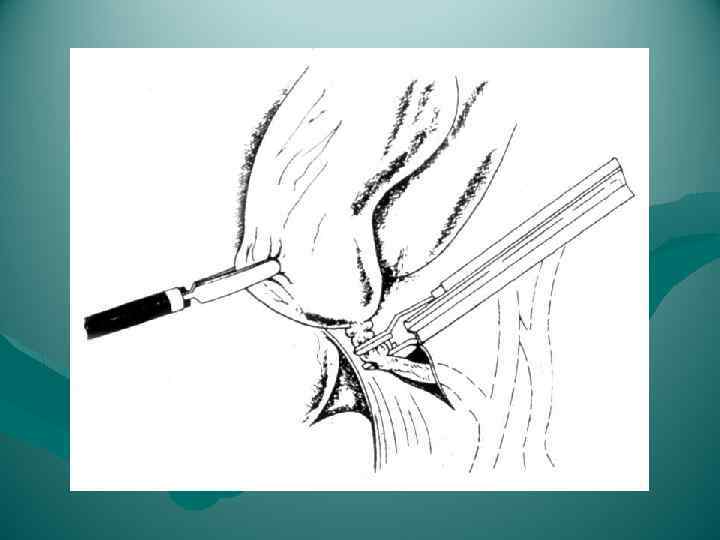

ЭТАПЫ ОПЕРАЦИИ ТИПИЧНОЙ ХОЛЕЦИСТЭКТОМИИ 1. Лапаротомия 2. Обнажение желчного пузыря 3. Выделение, перевязка и пересечение ductus cysticus и a. cystica 4. Выделение желчного пузыря из его ложа и удаление 5. Перитонизация ложа пузыря 6. Зашивание раны брюшной стенки ЭТАПЫ ОПЕРАЦИИ ЛАПАРОСКОПИЧЕСКОЙ ХОЛЕЦИСТЭКТОМИИ 1. Оперативный доступ 2. Выделение желчного пузыря из сращений с окружающими тканями 3. Выделение, клипирование и пересечение пузырного протока и пузырной артерии 4. Отделение желчного пузыря от печени 5. Извлечение желчного пузыря из брюшной полости

ЭТАПЫ ОПЕРАЦИИ ТИПИЧНОЙ ХОЛЕЦИСТЭКТОМИИ 1. Лапаротомия 2. Обнажение желчного пузыря 3. Выделение, перевязка и пересечение ductus cysticus и a. cystica 4. Выделение желчного пузыря из его ложа и удаление 5. Перитонизация ложа пузыря 6. Зашивание раны брюшной стенки ЭТАПЫ ОПЕРАЦИИ ЛАПАРОСКОПИЧЕСКОЙ ХОЛЕЦИСТЭКТОМИИ 1. Оперативный доступ 2. Выделение желчного пузыря из сращений с окружающими тканями 3. Выделение, клипирование и пересечение пузырного протока и пузырной артерии 4. Отделение желчного пузыря от печени 5. Извлечение желчного пузыря из брюшной полости

ЭТАПЫ ЛАПАРОСКОПИЧЕСКОЙ ХОЛЕЦИСТЭКТОМИИ 1. Оперативный доступ 2. Выделение желчного пузыря из сращений с окружающими тканями 3. Выделение, клипирование и пересечение пузырного протока и пузырной артерии 4. Отделение желчного пузыря от печени 5. Извлечение желчного пузыря из брюшной полости

ЭТАПЫ ЛАПАРОСКОПИЧЕСКОЙ ХОЛЕЦИСТЭКТОМИИ 1. Оперативный доступ 2. Выделение желчного пузыря из сращений с окружающими тканями 3. Выделение, клипирование и пересечение пузырного протока и пузырной артерии 4. Отделение желчного пузыря от печени 5. Извлечение желчного пузыря из брюшной полости